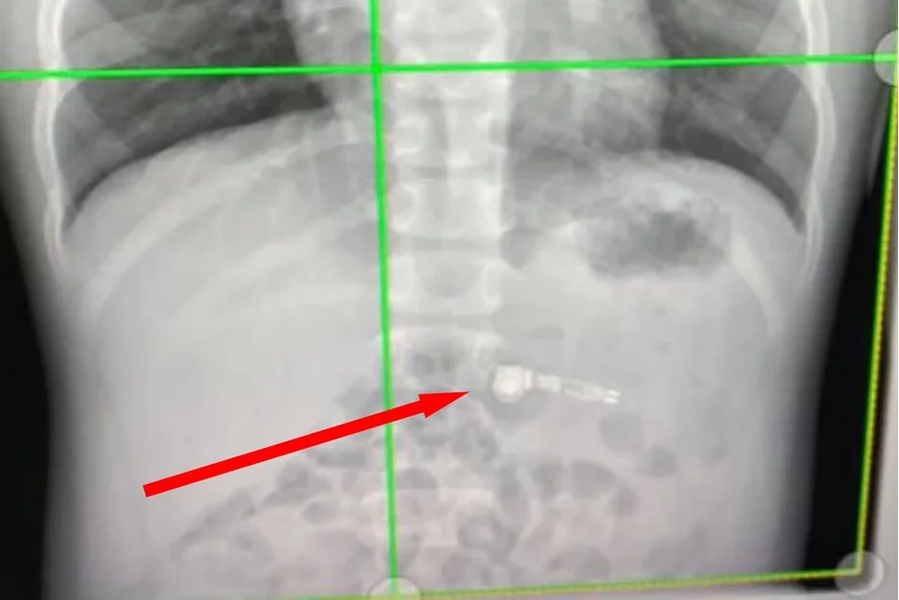

Мама рассказывает, что ее ребенок просто держал один наушник во рту за длинную часть, а потом проглотил, при этом она не успела отреагировать. Специалисты в отделе охраны здоровья детей Атланты были озадачены этим обстоятельством, обнаружив на рентгеновском снимке один из наушников AirPod.

Мать ребенка и сам мальчик были сильно обеспокоены тем, как будут доставать гаджет, но специалист заверил их, что AirPods выйдет естественным образом.